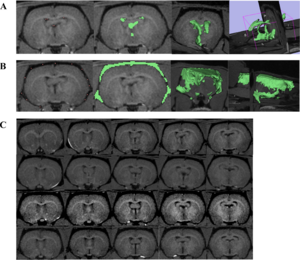

Publication: PLoS One. 2015 Dec 3;10(12):e0143821. PMID: 26633302 | PDF Authors: Gutierrez S, Descamps B, Vanhove C. Institution: Medical Image and Signal Processing Group, Ghent University-iMinds Medical IT department, Ghent, Belgium. Background/Purpose: Computed tomography (CT) is the standard imaging modality in radiation therapy treatment planning (RTP). However, magnetic resonance (MR) imaging provides superior soft tissue contrast, increasing the precision of target volume selection. We present MR-only based RTP for a rat brain on a small animal radiation research platform (SARRP) using probabilistic voxel classification with multiple MR sequences. Six rat heads were imaged, each with one CT and five MR sequences. The MR sequences were: T1-weighted, T2-weighted, zero-echo time (ZTE), and two ultra-short echo time sequences with 20 μs (UTE1) and 2 ms (UTE2) echo times. CT data were manually segmented into air, soft tissue, and bone to obtain the RTP reference. Bias field corrected MR images were automatically segmented into the same tissue classes using a fuzzy c-means segmentation algorithm with multiple images as input. Similarities between segmented CT and automatic segmented MR (ASMR) images were evaluated using Dice coefficient. Three ASMR images with high similarity index were used for further RTP. Three beam arrangements were investigated. Dose distributions were compared by analysing dose volume histograms. The highest Dice coefficients were obtained for the ZTE-UTE2 combination and for the T1-UTE1-T2 combination when ZTE was unavailable. Both combinations, along with UTE1-UTE2, often used to generate ASMR images, were used for further RTP. Using 1 beam, MR based RTP underestimated the dose to be delivered to the target (range: 1.4%-7.6%). When more complex beam configurations were used, the calculated dose using the ZTE-UTE2 combination was the most accurate, with 0.7% deviation from CT, compared to 0.8% for T1-UTE1-T2 and 1.7% for UTE1-UTE2. The presented MR-only based workflow for RTP on a SARRP enables both accurate organ delineation and dose calculations using multiple MR sequences. This method can be useful in longitudinal studies where CT's cumulative radiation dose might contribute to the total dose. |

Illustration of a CB-CT and five MR images of the same animal. a) Coronal CB-CT image and (b)-(f) biased field corrected and masked coronal MR images using a T1-weighted (b), T2-weighted (c), ZTE (d), UTE1 (e) and UTE2 (f) sequence. All CB-CT images were first co-registered using 3D Slicer version 3.6.3 by rigid body transformations using normalized mutual information. |